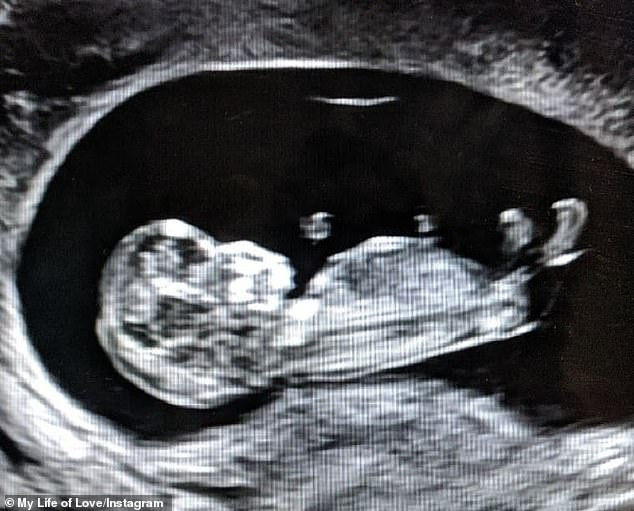

Înainte de Crăciun, Rachel a aflat că este din nou însărcinată. Însă și de data aceasta, fericirea ei și a soțului ei a fost umbrită. Cel de-al doilea copil nenăscut încă a fost diagnosticat cu aceeași boală.

”Am obținut rezultatele testului. Copilul este o fetiță frumoasă, dar care suferă de aceeași boală ca Mackenzie, prima fetiță”, a spus Rachael.

După aflarea teribilei vești, Rachael a trebuit să renunțe la sarcină.